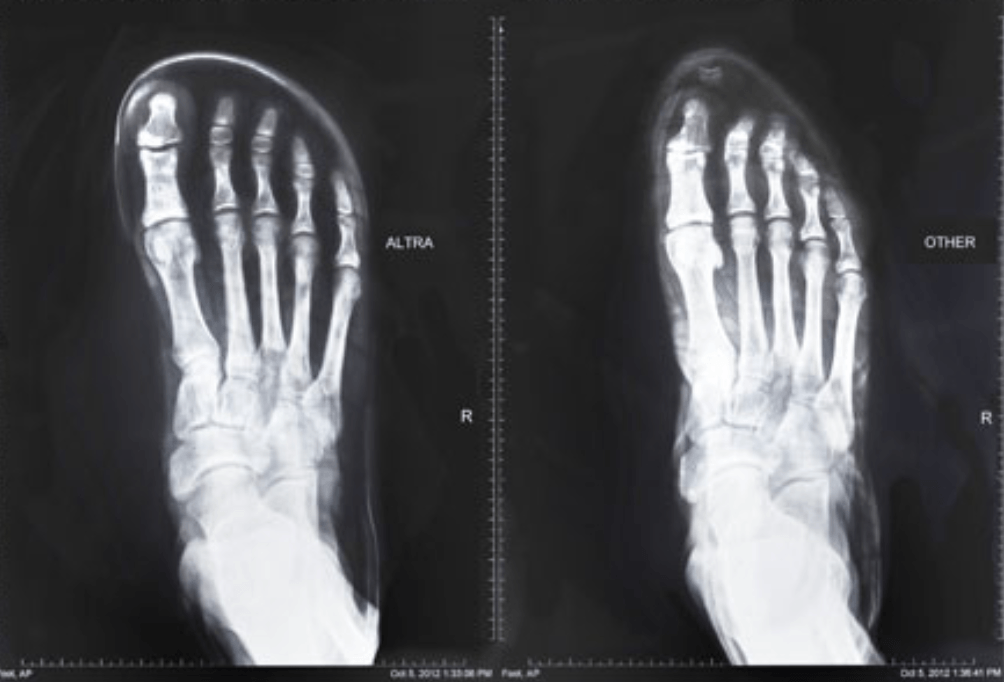

For centuries, humans were barefoot or wore thin, sandal-like protection. When shoes became popular in the mid-18th century, the design matched the shape of our feet: a wide toe box, minimal arch support, and a sturdy heel. It wasn’t until the 1970s and 1980s that shoes saw a major change. Over the past 50 years, the fashions and technological advances in footwear have changed the way our shoes are shaped and, in turn, are transforming the way our feet look, function, and feel. Most lifestyle and leisure shoes are built with high arches, narrow toe boxes, and stiff soles which claim to promote a cushioned step to reduce discomfort from standing, walking, and running.

Squeezing the ball of the foot into a tight or narrow toe box doesn’t allow for the natural spreading of the foot’s bones and muscles and can create overuse injuries. Many common issues seen from narrow toe boxes are bunions (lateral and medial), Morton’s Neuromas, and corns and calluses.